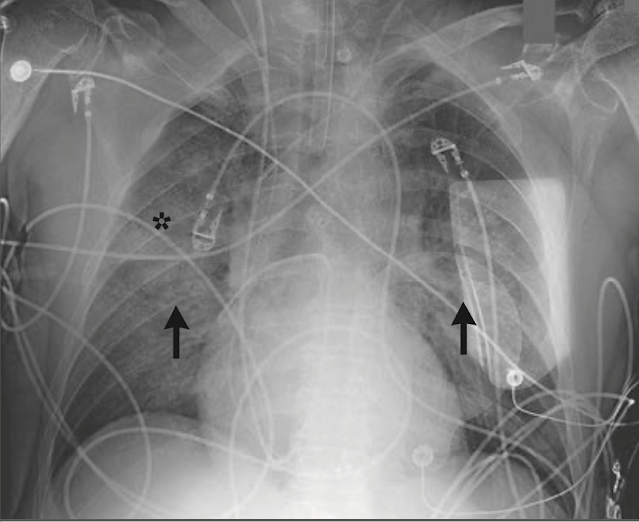

正面の胸部レントゲン写真は、肺水腫所見を認めた (図 2)

胸部 X 線写真では、右上葉気空間に不明瞭像(hazy opacity)とびまん性血管隆起があり、非対称性肺水腫を示唆する所見であった